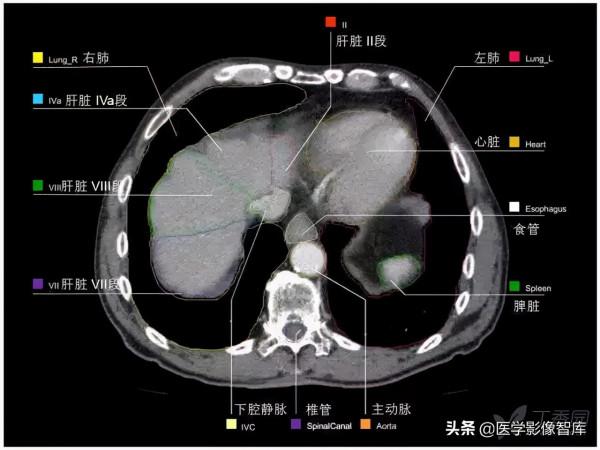

腹部CT